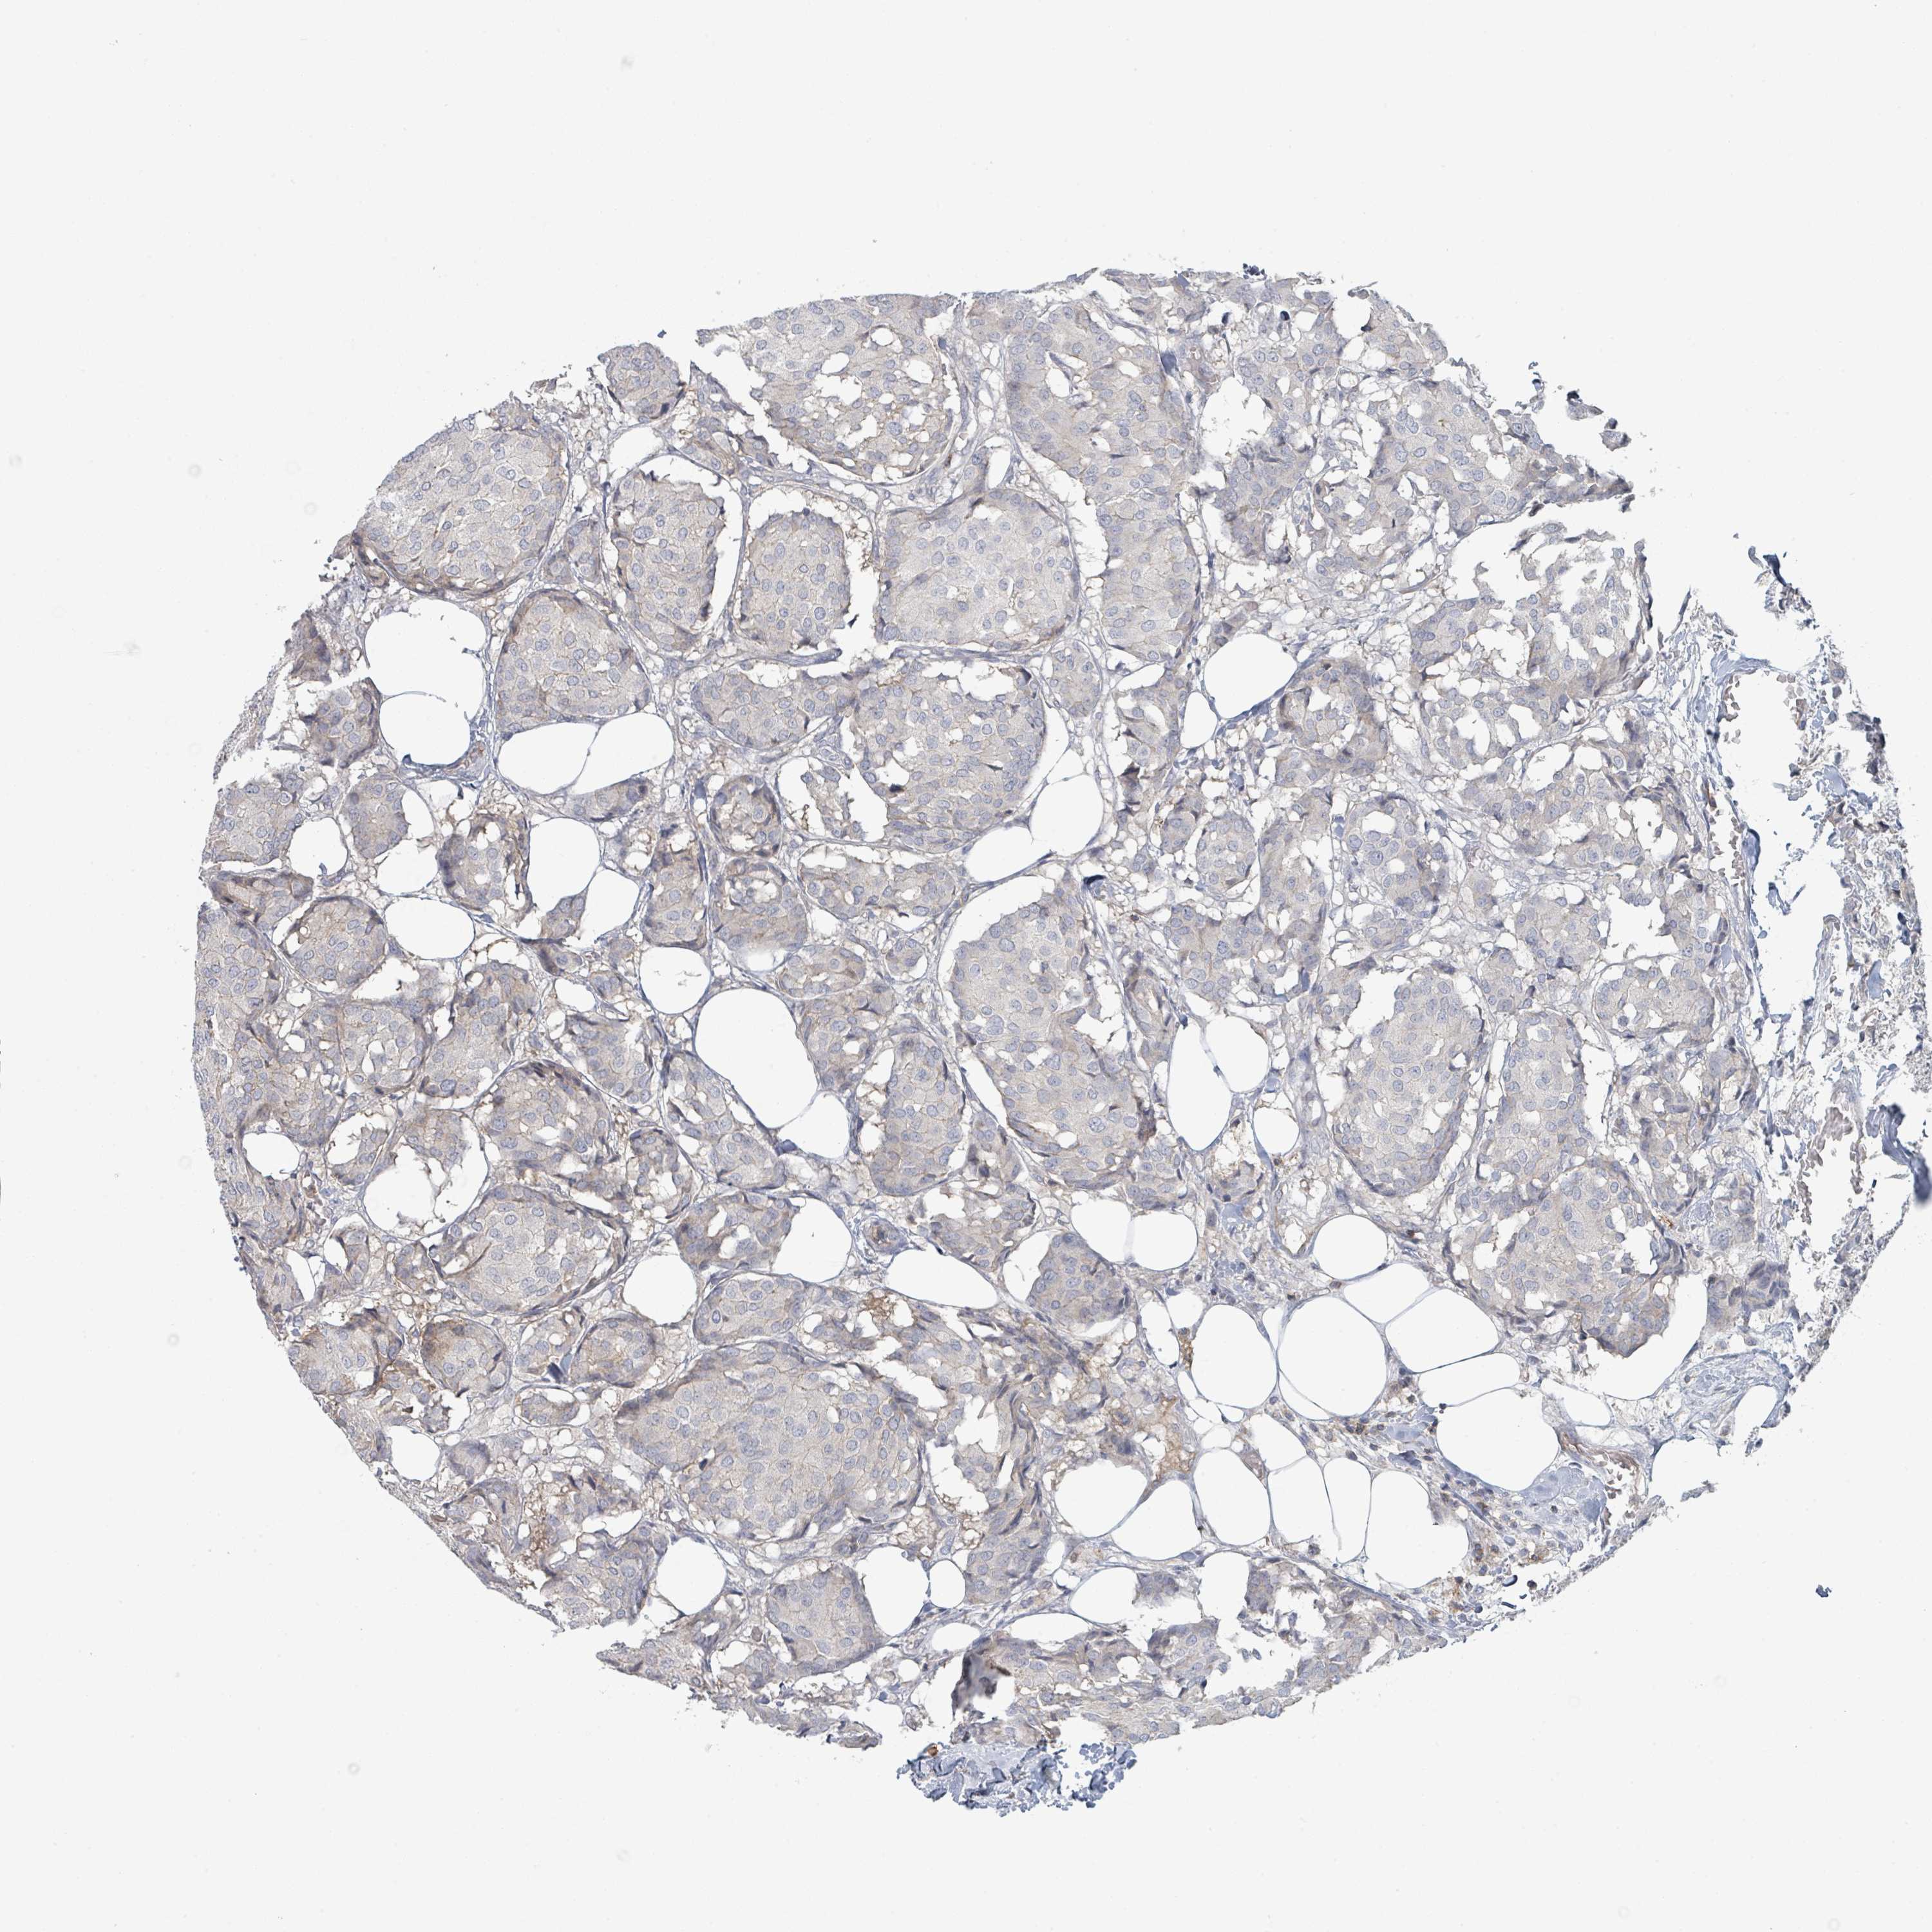

CANCER BREAST CANCER Show tissue menu

BRCA TCGA BRCA VALIDATION PROTEIN EXPRESSION